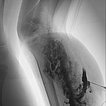

Contrast-enhanced MR angiography (MIP) shows complete enhancement of the venous malformation component in the left calf with contrast pooling.

The control MR angiography shows a clear improvement of the findings. Most of the dysplastic, dilated channels of the venous malformation are occluded.